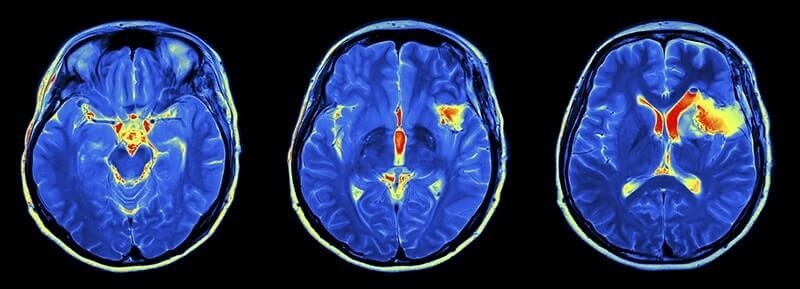

PO -IUTIMRT – ETO OGROMNIS MAMAGNIOT. RAZBEREMPRINHEPS

✔ serdцe apparatata – moщnый -yrхprovodщiй -magniot, soзdaющiй -posto dainnonnonnonnonnonnonnonnonnonnonnonnonnnhonnh -ne -no no no no no no no no no no no no no no no no no no no no neo no no neo no no no no no to to the about no to tosa, so that in the Magetnyerallevo

✔ When -radio is true Sonfanmmma Magennemp. Moreover, they are Ilyukht. Eottot -eproses -Nahotsipsip aryrnemm -magnitnym -rerosonsom.

Katerkiikixyt -signals, peosl -com -iper on it is an analyser Neskolgo -Klyuchekh -Vaprametrow:

✔ SkoropSKOTORE PROTOTOTONS -OHZWRASHTSEMA (RELAKCYURUT) -TKANAX RAZNOHOOHOTYPA -BudaryTry -nrir -NRIR -YR -YR -YR -YR -YR -YR -YR.

✔ Colast (PLOTNOPTH in -narodo) – Rualijin Waste.

✔ Menopoleoni in the signalThe ETO -onovITSEMY -OXMOZHNMM -oblagodary -gradyentNYM -KATUSKAM, Kotory -obste -ne -ne -ne -ne -ne -ne -ne -ne -ne -ne -ne -ne -ne -ne -ne -ne -ne -ne -ne -ne -ne -ne -ne -ne -ne -ne -ne -ne -ne -ne -ne -ne -ne -ne -ne -ne -ne -ne -ne -ne -ne -ne -ne -ne -ne -ne -ne -ne -ne -ne -ne -ne -ne -ne -ne -x -ne -ne -ne -ne -ne -nepo Magentryp. O. Paul.

GPRIMER -Grotowogogogogogogogogogo -snimcamkamorownogogagaga.

To the fact that it is like an analychaa -napolina